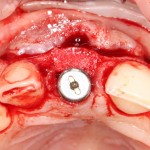

Устанавливается имплантат Astratech (Dentsply Implants):

Для аугментации также используем Bio-Oss Collagen 100 mg, нарезаем его по размеру с помощью скальпеля и позиционируем в лунках щечных корней:

На имплантат ставим формирователь, ушиваем лунку. Напомню, что любой биоматериал должен быть герметично запечатан в ране (фактор успеха III). В противном случае, от него больше вреда, чем пользы:

Совсем уж стягивать края раны не нужно (если бы мы использовали обычный Bio-Oss, то это было бы необходимо). Отличие Bio-Oss Collagen еще и в том, что он не размывается при кровотечении.